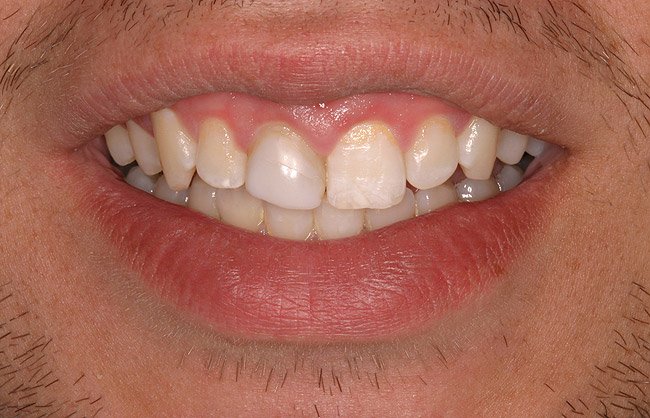

Figure 5a  Congenitally missing lateral incisors. Postorthodontic therapy, prior to implant placement.

Figure 5a

Figure 5b  Congenitally missing lateral incisors. Postorthodontic therapy, prior to implant placement.

Figure 5b